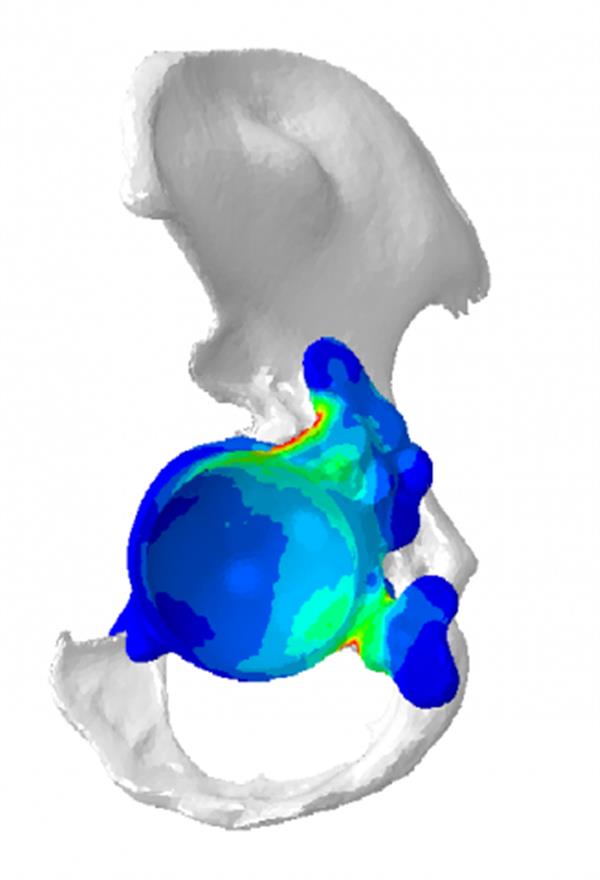

Mobelife团队为Fellesen设计了一个与她的臀部结构完全相匹配的定制化植入物。为了此次手术,该团队使用了医疗3D打印软件3-matic,,该软件允许用户直接在三角面上展开工作。他们还为Fellesen设计了一个定制的凸缘,并确定了螺钉的位置。为了支撑螺钉,他们用Mimics里CT数据的灰度值对Fellesen的骨质量进行了分析。 此外,为了确保植入物和骨组合能承受髋关节的多次运动和压力,Mobelife团队进行了一次有限元分析(FEA)。一名外科医生验证了最终的设计,随后该设计被导出并被3D打印。他们用钛合金在一台LayerWise 3D打印机打印出植入物。